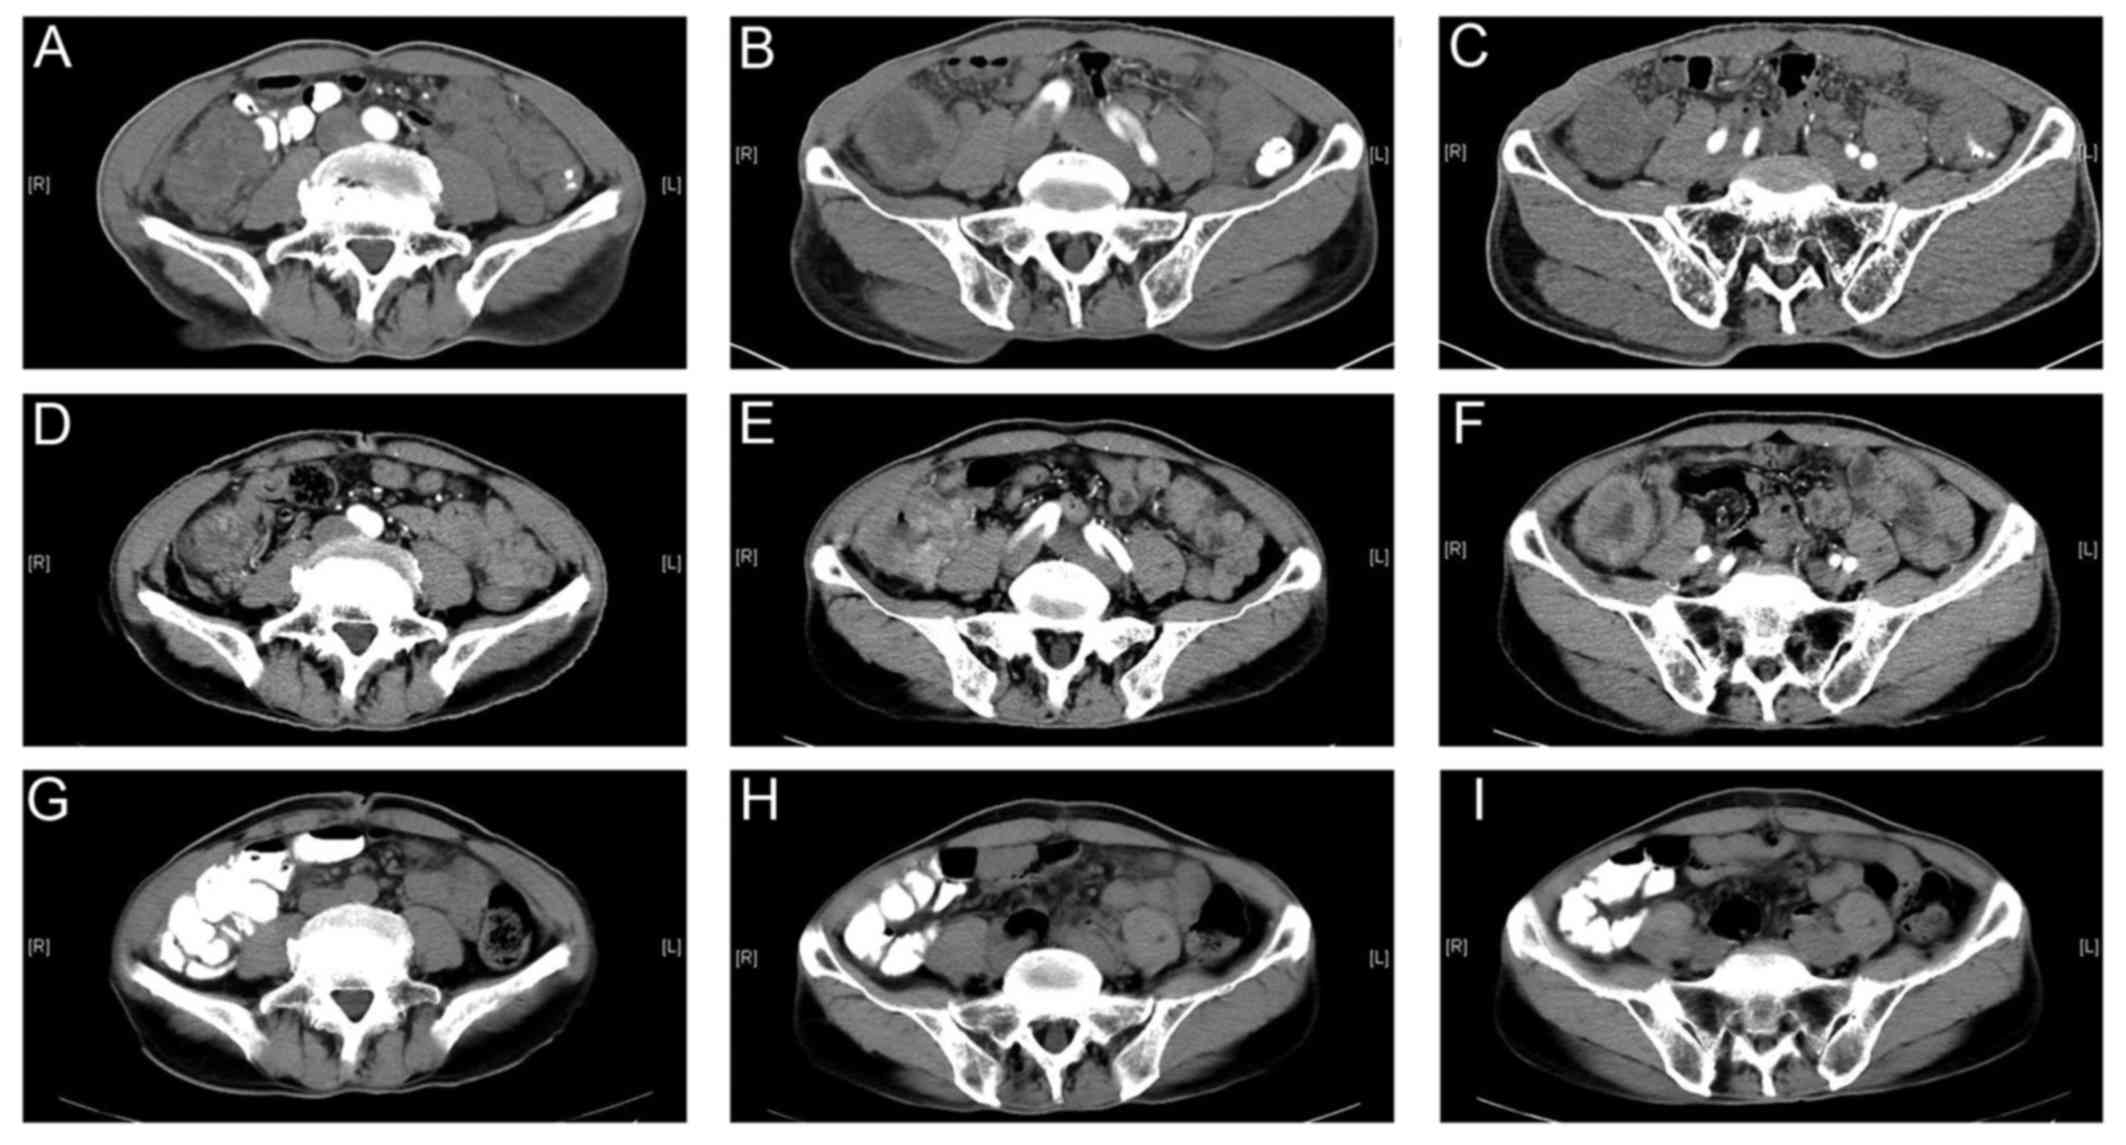

Abdominal Ct Scans In Series Indicating The Sigmoid Colon Cancer Download Scientific Diagram

www.researchgate.net